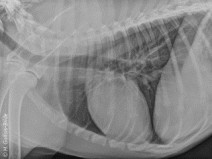

• Travaux pratiques de radiographie / Le Thorax

Le GEIM vous propose une séance de travaux pratiques de radiographies sur le thorax. Tous les aspects sont abordés sous la forme de TP de lecture de radiographies numériques sur station de travail Osirix sur Mac (3 vétérinaires maximum/ordinateur).